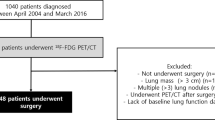

Patient selection

We asked all consecutive patients with a diagnosis of IPF, with a typical usual interstitial pattern (UIP) on high resolution CT of the chest (HRCT), to undergo [18F]FDG PET. According to ATS/ERS/JRS/ALAT guidelines, a typical UIP pattern was defined as the combination of reticular abnormalities, honeycombing with or without traction bronchiectasis, predominantly localized in sub-pleural areas with absence of features listed as inconsistent [19]. Patients receiving oral corticosteroids, immunosuppressants, or any antifibrotic therapy (including pirfenidone and nintedanib) within 3 months before PET completion were excluded. All patients received a diagnosis after a multidisciplinary discussion involving review of all clinical, functional, imaging and pathological data, according to French and international guidelines [19, 20]. Former smokers were defined by smoking cessation for at least 6 months.

We included 27 patients with IPF (mean age 65.3 ± 12.4 years) (Table 1): 11 were never smokers, four were current smokers and 12 were former smokers. The mean duration of IPF since diagnosis was 2.9 ± 2.7 years at the time of PET scan completion. Mean follow-up was 1.6 ± 0.9 years after PET scan. At the time of the PET scan, seven patients (26%) were in GAP stage I, 12 (44%) in GAP stage II and 8 (30%) in GAP stage III. Mortality during follow-up was 44% (n = 12), with a median survival of 839 days. The main cause of death (n = 11) was respiratory failure. Four patients experienced an acute exacerbation during follow-up. Lung cancer developed in one patient 2 years after evaluation. Follow-up evaluation of pulmonary function tests was available for 22 patients; three were lost to follow-up and two died before the completion of follow-up evaluation.